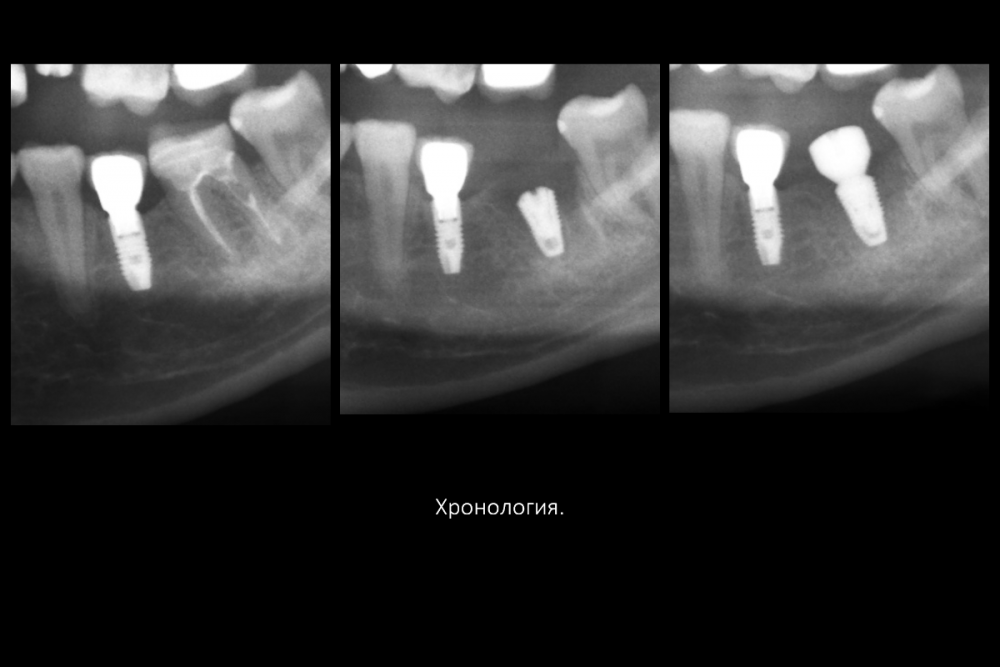

Карен Аванесов Опубликовано 16 июля, 2021 Поделиться Опубликовано 16 июля, 2021 Вариант герметизации послеоперационной раны, когда, хочется установить имплантат и сократить для пациента сроки реабилитации. Итак, "Астра" отличные имплантаты при хороших условиях работают, при экстремальных ситуациях выбор калибров сильно страдает и суживает возможности оператора (очевидно менеджерам не интересно будущее системы, эксклюзивная цацка профайл и маркетинговое продвижение на "озоне" это не то), как по мне, раздутый, абсолютно не удобный хирургический набор, не разделяю восторгов относительно эксклюзивности и предписуемым волшебным свойства, кость наросла! это только на "астре" так или только на анкилозе! На любой системе можно получать результаты. Представляю клинические случаи с одинаковыми условиями, но разными системами, там где "астра" не захотела первичной стабильности, в виду недостаточно широкой талии, "дентиум" диаметром 6мм встал бы на ура, но "астра" такой заказ ортопеда. 8 1 1 3 Ссылка на комментарий

Карен Аванесов Опубликовано 21 февраля, 2022 Автор Поделиться Опубликовано 21 февраля, 2022 Дозрела костна ткань. Возвращаясь к вопросу о "волшебстве" брендовых систем.... Безусловно, молодому специалисту, через сопливый нос бубнить на консультации что от СТАВИТ страуманн, мобель или аштру, поднимает самомнение, окрыляет, иногда и до звездной болезни, помогает быстрее "заматереть,"но сути не меняет. Кость "подрастает" не только аштре например, что иногда демонстрируют с восторгом, но и на отстойном дентиуме тоже, и думаю и на отстойной альфа-био и т.д., т.е. все-же от условий зависит, пациента и конечно техника, что там как и дальше будет. Соберу кейс покажу вошебный рост на голых витках корейского народного ширпотреба)))) 1 Ссылка на комментарий